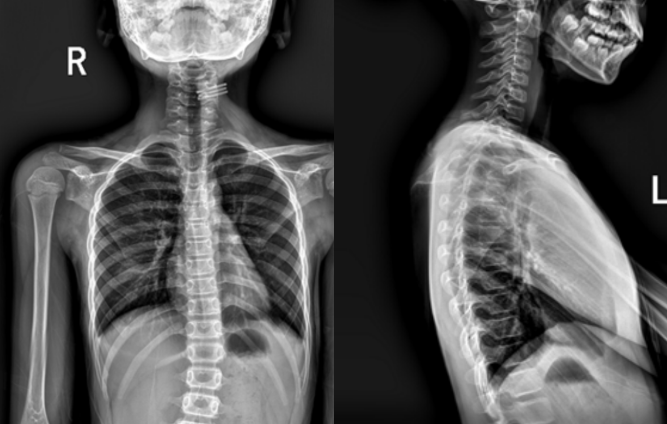

② X光片檢查:這是診斷脊柱側(cè)彎的“金標(biāo)準(zhǔn)”。通過(guò)拍攝全脊柱X光片,可以確定側(cè)凸的類型、部位、嚴(yán)重程度和柔韌性,有助于判斷病因,進(jìn)行術(shù)前設(shè)計(jì)。

● 確診:明確是否存在脊柱側(cè)彎。

● 測(cè)量角度(Cobb角):精確測(cè)量彎曲的嚴(yán)重程度,這是決定治療方案的核心依據(jù)。

● 評(píng)估骨骼成熟度(Risser征):通過(guò)觀察骨盆的骨骺閉合情況,判斷孩子的生長(zhǎng)潛能,這對(duì)于預(yù)測(cè)側(cè)彎進(jìn)展至關(guān)重要。